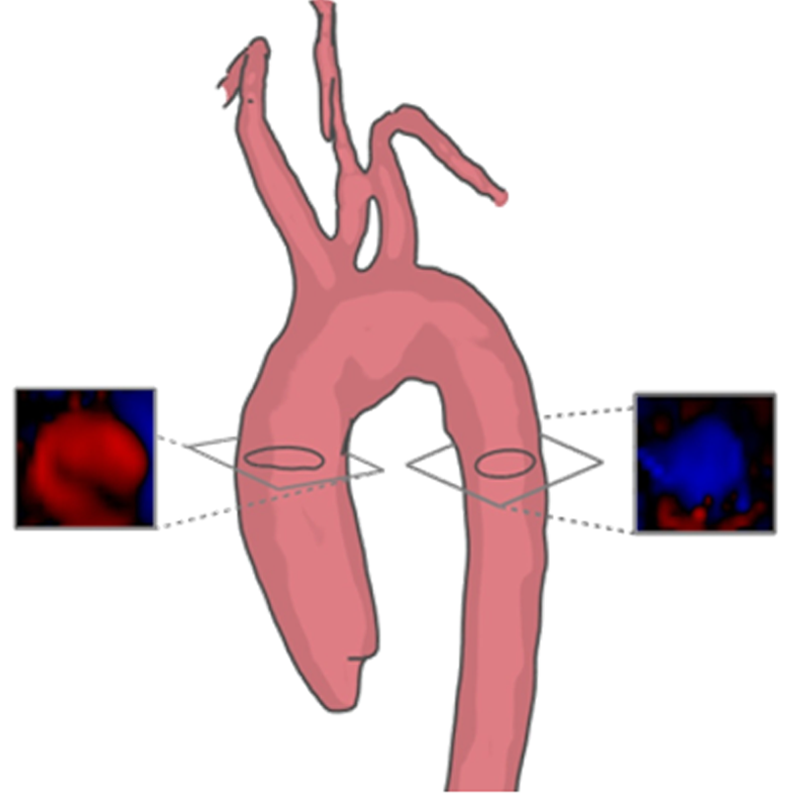

The visual exploration of blood flow data is usually focused on a rather small anatomical region. In case of simulated blood flow data, this represents the domain where the simulation was performed. It may be necessary to present this focus region embedded in a somehow larger context to better understand the location of a pathology and the in- and outflow regions. Such a visualization goal may be achieved with a coordinated focus-and-context view, where the detail view presents only the target region and the context view provides the big picture with additional anatomical context. An integrated focus-and-context view is mentally easier to interpret. A reasonable strategy is to employ distance-based transfer functions Tappenbeck_2006_SimVis , where the distance to the target anatomy is mapped to opacity in order to hide distant vascular structures. This strategy is illustrated in Figure 3. The specific choice of colours and opacity as well as the amount of information to be displayed requires careful discussions with physicians Neugebauer_2009_CARS . Such a visualization may be a first step in a pipeline of exploration and analysis, as it presents an overview and needs to be followed by a more local analysis.

Van Pelt et al. Pelt:2010 presented an anatomical context based on methods inspired by medical illustrations, where the detail is removed while the morphological information is preserved(see Figure 5). To this end, they used cel-shaded silhouettes, combined with superimposed occluding contours. Hidden contours were visible during viewpoint interactions in order to resolve occlusion problems and to clarify spatial relations. Their user evaluation showed that these methods had a positive impact for the purpose of anatomical context representation of the flow.

A widely used geometric descriptor is the vessel centerline, determined by a skeletonization algorithm (see, e.g., Kirbas:2004 ). The vessel centerline is often used in order to move a cross-sectional plane that is always aligned perpendicular to the centerline, presenting the maximum-sized area. In conventional vessel analysis packages, the cross-sectional view displays the intensity values from the original image data, e.g., the CT Hounsfield values. In case of blood flow data, this strategy may be used to present any scalar value derived from the flow or the flow data itself, e.g., by using some glyph mapping. Van Pelt et al. Pelt:2010 presented this cross-sectional visualization approach for the main arteries (see Figure 5).

Van Pelt et al. Pelt:2010 presented a semi-automatic technique to probe cross-sections of anatomical data avoiding full segmentation ( see Figure 5). If anatomical data is not available an option for cross-sectional placement is to use the so called temporal maximum intensity projection (TMIP). For each voxel position of the TMIP scalar volume, the maximum speed is determined along the time axis of the 4D flow data. Hence, each voxel with a bright intensity indicates that a flow velocity with a substantial speed has occurred there at least once during the cardiac cycle. This probing method has several drawbacks: it assumes tubular structures, so it is only valid for vessels, and it does not consider the movement of the vessels during the heart cycle.